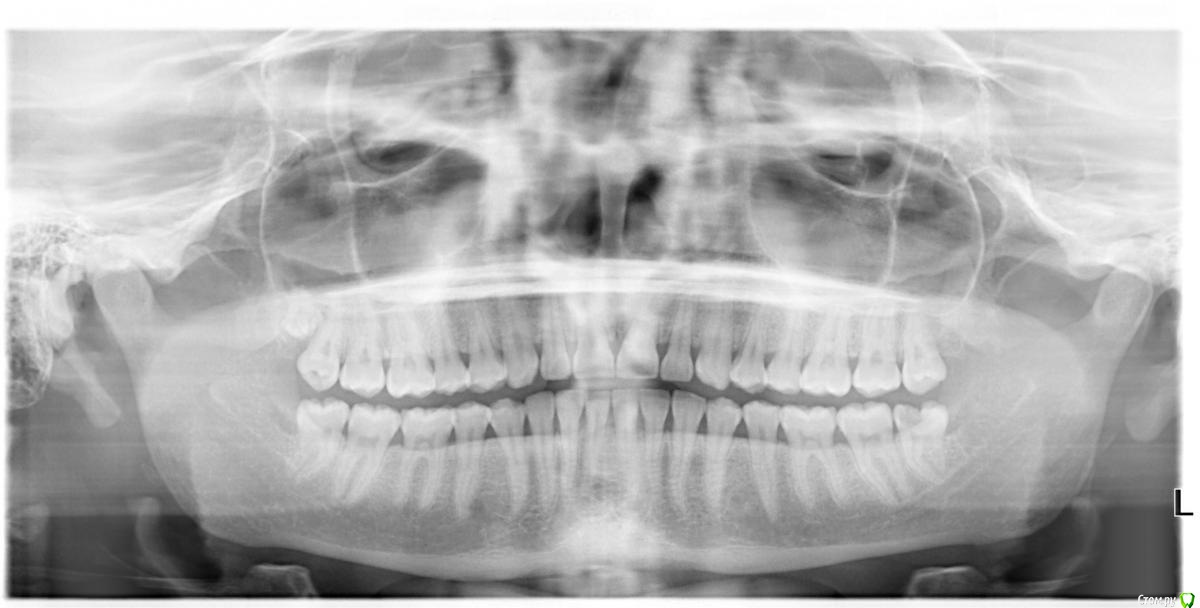

Оксана Мирзаева Опубликовано 16 января, 2019 Автор Поделиться Опубликовано 16 января, 2019 Вот снимок перед удалением И шишка с покраснением Ссылка на комментарий

Оксана Мирзаева Опубликовано 16 января, 2019 Поделиться Опубликовано 16 января, 2019 ! В воскресенье 13.01 удалила нижнюю восьмерку слева. Удаление было сложным. Длилось три с половиной часа. Стоматолог почему то не разрезал десну, а расковырял ее. Коронка была частично разрушена, удаляли по частям. Последний загнутый корень очень долго доставали. Когда мне в четвёртый раз докололи анестезию, у меня перестал моргать левый глаз, вообще левая половина лица будто онемела. Врач сказал выпить дома антибиотик, супрастин, обезболивающее и лечь спать. С полуоткрытым глазом я уснула, проснулась через 2,5 часа с дикой болью в ухе и горле при глотании. Из за неудачного положения зуба, врач инструментом натягивал мне уголок губы, в итоге она порвалась. Рот я не могла раскрыть больше чем на 2см., думала что из за губы. В последующие 2 дня стало хуже, отек на лице не сходил, причём появился он не на месте 8ки, а чуть дальше к подбородку. Шишка твёрдая при пальпации болезненная, когда открываю рот происходит будто натяжение от шишки до самого уха и очень больно. К вечеру на месте шишки появилось красное пятно (утром уже не было). Не могу полностью наклонить голову вправо-болят мышцы шеи слева. На лунке и щеке рядом белый налёт. Сегодня врач почистил под анестезией. Про шишку сказал инфильтрат и отправил резать вотделение челюстно-лицевой хирургии. Подскажите пожалуйста что со мной!!! Мой чудо стоматолог на все мои вопросы отвечает лишь что у него также было Ссылка на комментарий